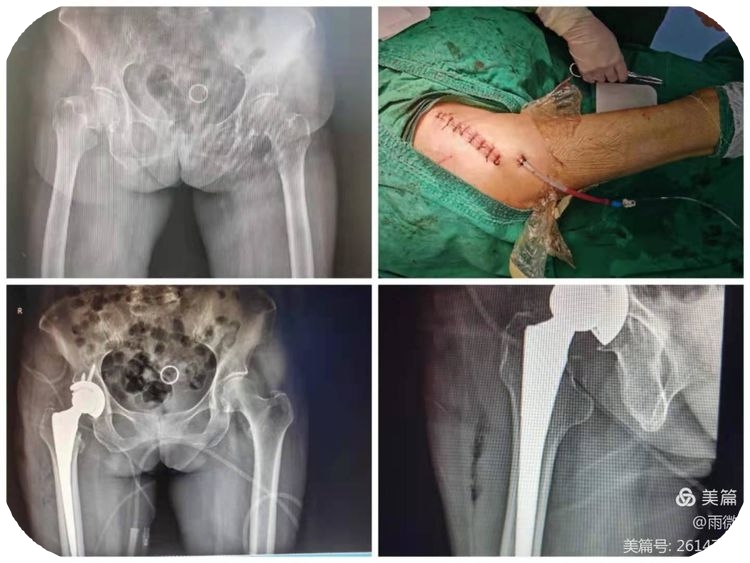

微创COM入路全髋置换治疗

微创COM入路全髋置换治疗老年人股骨颈

骨折、微创手术、损伤小、患者恢复快